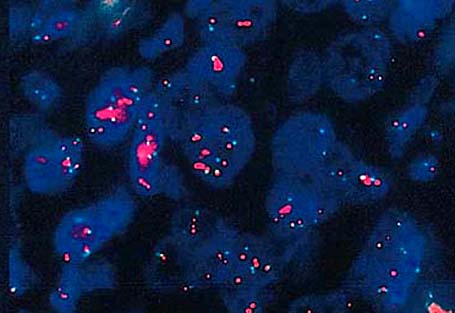

Molecular / cytogenetics description

- ER+ pathway: characterized by gains of 1q, loss of 16q, sometimes amplification of 17q12

- ER- pathway: characterized by loss of 13q, gain of 11q13, amplification of 17q12, p53 mutations common, increased expression of genes associated with cell proliferation

- PI3KCA mutations associated with endocrine therapy resistance (Virchows Arch 2016;469:35, Int J Breast Cancer 2020;2020:3759179)

- p53 mutations in many basal-like tumors (Nature 2012;490:61)

- HER2 gene amplification in approximately 15% (Cancer Res 1993;53:4960, J Clin Oncol 1989;7:1120)

- Gene expression profiling stratifies breast cancers into several intrinsic molecular subtypes (e.g., luminal A, luminal B, HER2 enriched, basal-like, etc.) (Nature 2012;490:61)

- 5 - 10% of breast cancers are hereditary as result of mutations in various genes, such as BRCA1, BRCA2, TP53, STK11, CD1, PTEN, MDM2, RB, CHEK2 (Acta Oncol 2019;58:135)

- ESR1 mutations associated with resistance to endocrine therapy (JAMA Oncol 2016;2:1310)

Molecular / cytogenetics images